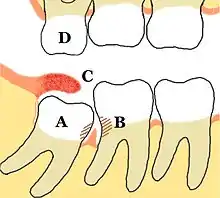

Impacted wisdom teeth are classified by the direction and depth of impaction, the amount of available space for tooth eruption and the amount of soft tissue or bone that covers them. The classification structure allows clinicians to estimate the probabilities of impaction, infections and complications associated with wisdom teeth removal.[26] Wisdom teeth are also classified by the presence of symptoms and disease.[27]

Treatment of an erupted wisdom tooth is the same as any other tooth in the mouth. If impacted and having a pathology, such as caries or pericoronitis, treatment can be dental restoration for cavities and for pericoronitis, salt water rinses, local treatment to the infected tissue overlying the impaction,[28]: 440–441 oral antibiotics, surgical removal of excess gum flap (operculectomy), or if those failed, extraction or coronectomy.